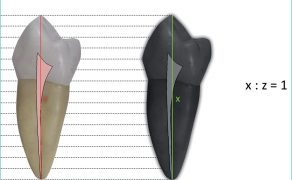

Streszczenie: Zarówno w technologii cyfrowej, jak i analogowej zdjęcia wewnątrzustne można wykonywać za pomocą dwóch technik: izometrii Cieszyńskiego i kąta prostego. Do wykonywania zdjęć techniką kąta prostego stosowany jest specjalny uchwyt do pozycjonowania detektora obrazu rtg. w jamie ustnej. Otrzymywane w ten sposób obrazy są powtarzalne, możliwe są więc ich porównywanie i analiza komputerowa. Wadą metody jest powiększenie obrazu ze względu na oddalenie detektora od obiektu badanego.

Summary: Digital and analog periapical radiographs may be performed using the bisecting angle (Cieszyński) technique, or the paralleling technique. In paralleling technique a special holder is used for positioning of x-ray detector. Images taken in this way are repetitive, can be compared and computer analyzed. The limitation of this method is enlargement of radiograph due to the increased distance between the detector and the examined tooth.

Technika kąta prostego zwana jest też techniką równoległą – paralleling technique. Jej podstawową zasadą jest umieszczenie detektora promieniowania rtg. równolegle do osi długiej zębów i rzutowanie się promienia centralnego pod kątem prostym do osi długiej zębów i detektora promieniowania. Ogranicza to do minimum zniekształcenie obrazu. Istotne jest również zwiększenie odległości pomiędzy źródłem promieniowania a [...]